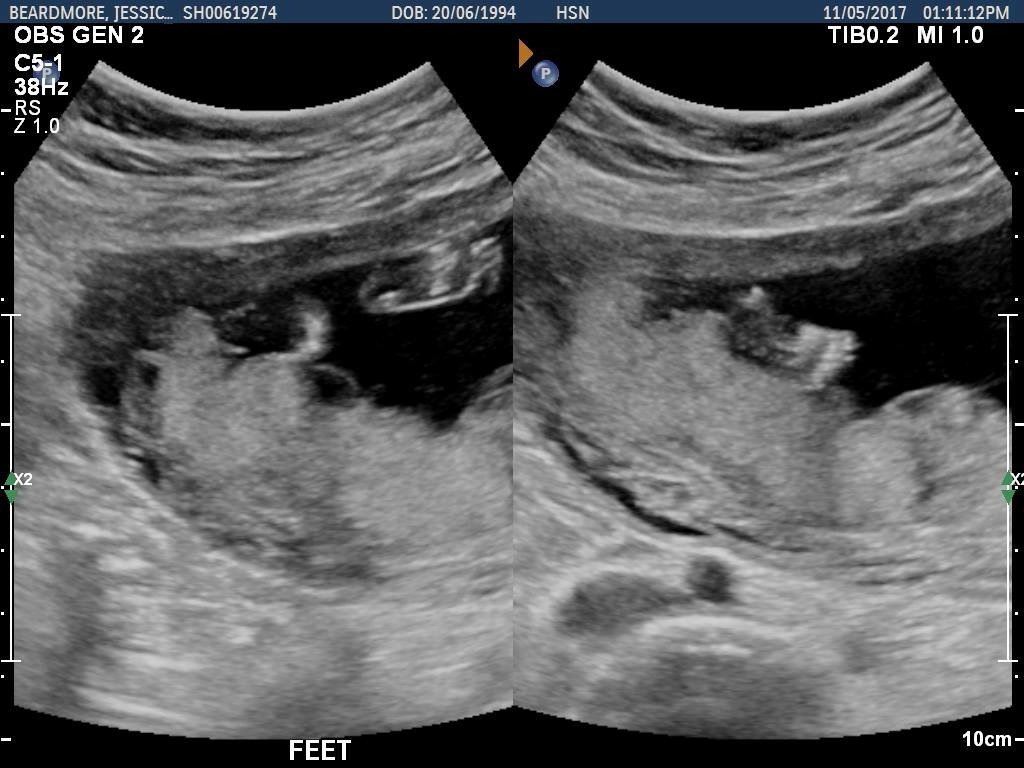

Can anybody guess a gender from these pictures? :) Come on mommies!! Heheh! Head shots and head/body.